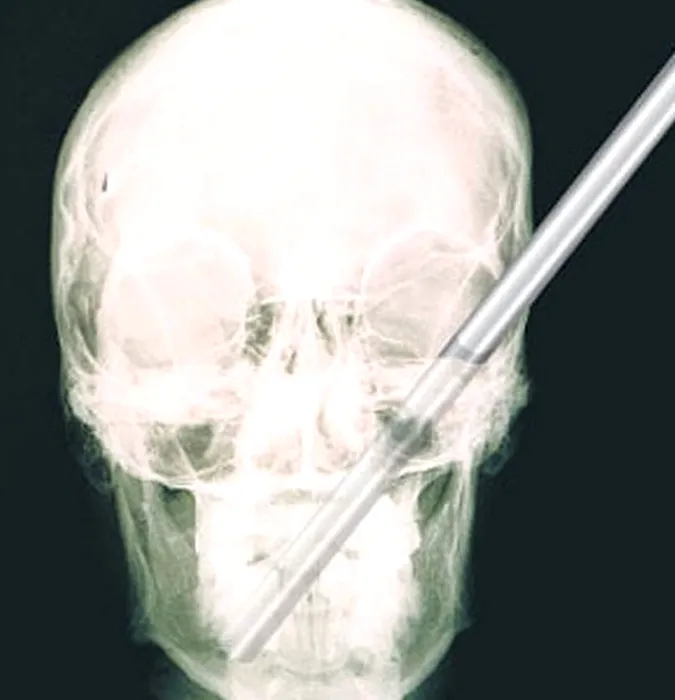

GALERIE FOTO: Cele mai terifiante radiografii